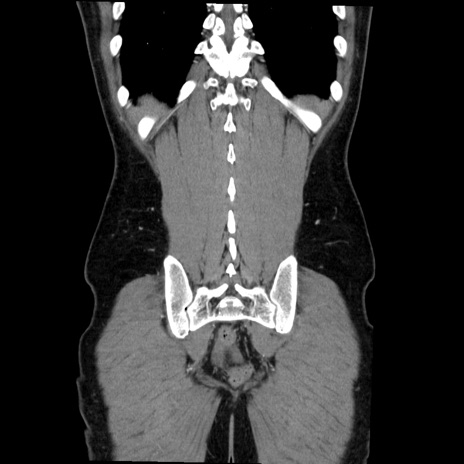

症例36(冠状断像)

【症例】20歳代 男性

【主訴】心窩部痛

【現病歴】今朝より上腹部痛あり。一旦軽快していたが再度出現したため救急要請。昨日夕に白身の魚を含む刺身を食べた。

【身体所見】BP 136/89mmHg、HR 74/min、BT 37.0℃、腹部:膨満、軟、心窩部に圧痛あり。反跳痛なし、筋性防御なし、腸雑音やや亢進あり。

【データ】WBC 17700、CRP 0.48